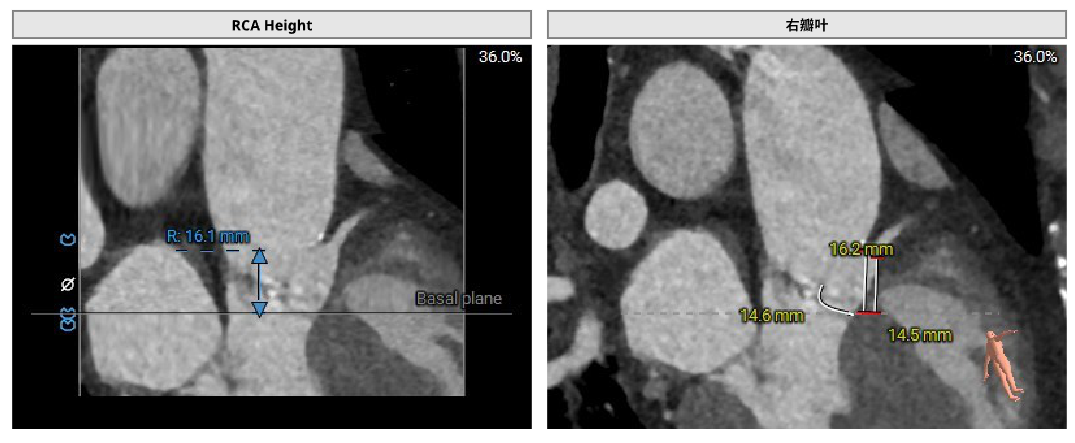

患者男性,77岁,三叶瓣。主动脉瓣重度狭窄,术前平均跨瓣压差48mmHg,峰值流速4.6m/s。瓣环及瓣叶钙化,瓣环面积径23.4mm。左冠高度11.8mm,右冠高度16.5mm。外周入路未见明显钙化,内径尚可。

手术经右侧股动脉入路,使用19mm球囊预扩,术中植入23# RENATUS®球扩式经导管主动脉瓣。输送器顺利通过,瓣膜精准释放,术后即刻平均跨瓣压差由48mmHg降至5mmHg,术后峰值流速由4.6m/s降至2.0m/s。瓣膜释放位置理想、形态及功能良好,无外周血管损伤,术后无明显瓣中及瓣周反流等并发症。